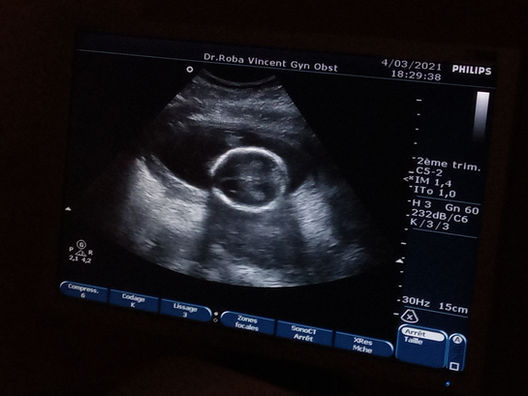

La deuxième echographie

Et voilà, la deuxième échographie ! T'as vu comment j'ai grandi?

Je fais maintenant 4 cm, et je commence à ressembler à un bébé.

J'ai une tête, un cerveau, une colonne vertébrale et un début de cordon ombilical.

Maman peut maintenant fièrement dire qu'elle a deux cerveaux ! Ouverture du débat : "Cela permet-il de réfléchir deux fois plus vite ?"

Maman en fait du bon boulot ! Je suis en super santé et tout se présente super bien. Elle a donc reçu les félicitations du doc et de Papa !

Il paraît que je bouge beaucoup... Est-ce que le sport sera mon truc, comme mes parents ? :D

Ou peut-être que je prépare une carrière dans le cinéma, vu comme je m'active devant la caméra ?

En tout cas, Papa et Maman sont impressionnés, et seront fiers de moi quel que soit le chemin que je choisirai!

Très bonnes dernières paroles du docteur pour conclure cette session : "Voilà, c'est parfait !"